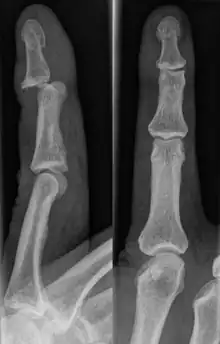

There are a variety of possible signs indicating a jammed finger. These depend on the severity of the injury.[3] They may include swelling, reduced joint flexibility, pain, tenderness, and joint deformity.[1] There may also be discoloration of the skin due to bruising. These symptoms usually persist for a few weeks.[3] In some cases, the damage and its effects can last for years.[4] Initial signs of a dislocation include abnormal bumps or projections at the joint. There may also be an audible popping noise when the injury occurs.[5] Fractures are indicated by abnormal protrusions along the bone,[6] where the bone itself appears split or twisted.

Fractures

Fractures are instances where the bone's structural integrity has been compromised.[20] If a jammed finger produces a fracture, pain will be greatest at the bone as opposed to the joint.[2] There may also be visual deformation of the bone itself.[6] As with any skeletal injury, an x-ray can be conducted to verify the presence of a fracture.[1] The distal phalanx is especially vulnerable to avulsion fractures.[1] These avulsion fractures are common following a first time dislocation of the DIP.[1]